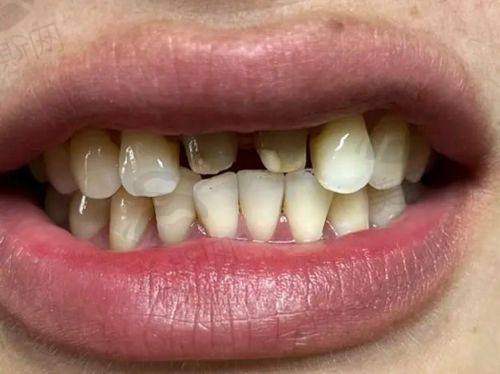

4. 美学修复:全瓷牙冠(色泽自然,媲美真牙)、瓷贴面(微创改善牙齿着色、间隙),适合前牙美观修复;

实例2:隐形矫正改善“地包天”,自信笑对工作